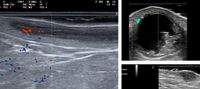

Ecoguiado de neuromoduladores estéticos

¿En qué consiste el curso? Aprende a hacer infiltración ecoguiada de medicación estética, a través de la inyección de neuromoduladores, una de sus principales aplicaciones clínicas. Aumenta la seguridad y la eficiencia de tus tratamientos, y reduce los riesgos de efectos adversos, usando la ecografía en tiempo real como ayuda.

¿A quién va dirigido este curso? Licenciados o Graduados en Medicina, con Máster en Medicina Estética (mínimo de 60 créditos ECTS). Es recomendable alguna formación o experiencia previa en ecografía estética, pero no es imprescindible. El curso se realiza en la clínica del alumno en Islas Canarias, resto de España o Portugal, para posibilitar hacer el curso con pacientes reales del alumno.

¿Qué obtengo de este curso? Aumenta la seguridad y la eficiencia de tus tratamientos médico estéticos y reduce los riesgos de efectos adversos, gracias al control ecográfico en tiempo real.